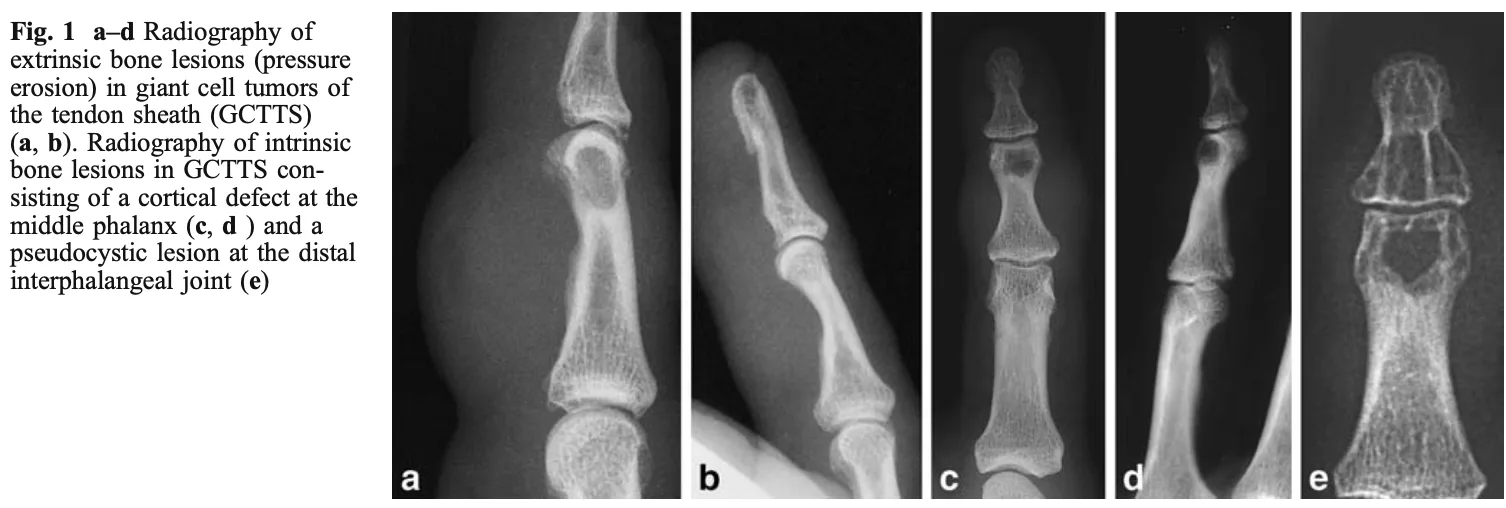

腫瘍に圧されて骨が凹んだり(a, b), 腫瘍が骨に食い込んで孔が開いたり(c, d, e)します.

1年前から薬指に腫瘍があり, X線写真では指の骨骨の圧痕や侵食像が認められました. 腱滑膜から発生した『腱滑膜巨細胞腫 tenosynovial giant cell tumor(TGCT)(または, 腱鞘巨細胞腫 giant cell tumor of tendon sheath(GCTTS)』という良性軟部腫瘍が疑われました.